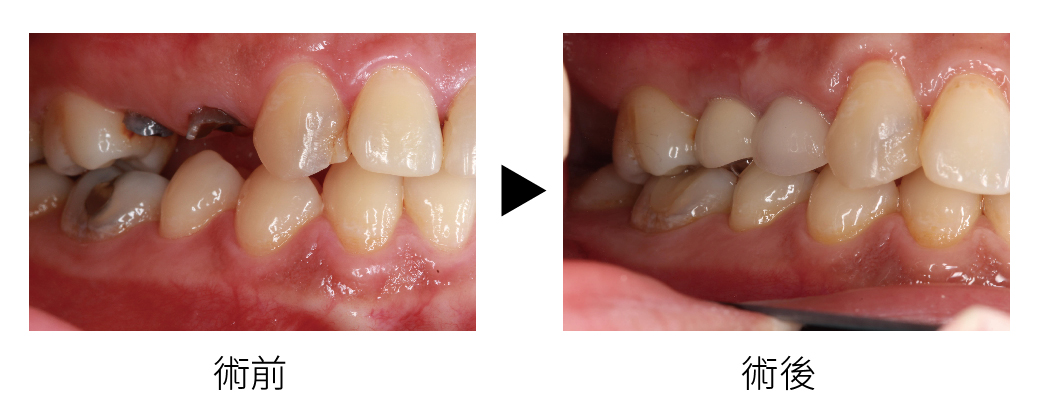

這位患者是一位三十多歲的女性,主訴為右上第一小臼齒(14)、右上第一小臼齒(15)殘根、前牙區左上犬齒(23)缺失已經有一段時間。她在初診時坦言,因為缺牙不僅讓她在咀嚼食物時感到不便,更重要的是大大影響了她的外觀和自信心。她跟我分享,過去和朋友聚會或工作場合需要近距離交談時,總是會因為擔心別人注意到自己的缺牙而感到尷尬,有時甚至會下意識地用手遮住嘴巴,就連拍照也很少露齒微笑。

她最大的期待就是能夠恢復自然、美觀的門牙,希望自己能夠像以前一樣自在地微笑和說話,在詳細檢查與評估後,我發現她缺失的是左上犬齒(23),鄰近的牙齒結構尚完整,但因長期缺牙,局部齦骨已有輕度萎縮,且對應位置的齦乳頭稍有下降,因為在整體美觀問題,也建議可以透過全瓷美白貼片來改善黃牙的問題。此外整體口腔衛生良好,並無嚴重牙周病或其他活動性病灶。

回診時植體與骨頭結合良好,我們進一步進行數位取模,設計專屬於她的全瓷美學牙冠、與全瓷美白貼片。安裝正式假牙時,特別調整顏色、透明度及形態,使其與周圍自然牙齒幾乎無法分辨。患者在鏡子前看到新的門牙時,臉上立刻露出久違的自信笑容。她說,終於可以自在地開懷大笑,不再因為缺牙而感到困擾。

術後追蹤半年,植體周圍組織穩定,患者口腔衛生維持良好,上排牙齒則煥然一新,擁有理想的微笑曲線和更亮白的色澤。她表示,不僅飲食習慣恢復正常,心理壓力也減輕許多,整個人變得更有自信、積極面對生活。她感謝我們團隊的細心與專業,並樂於推薦親友來診所諮詢。